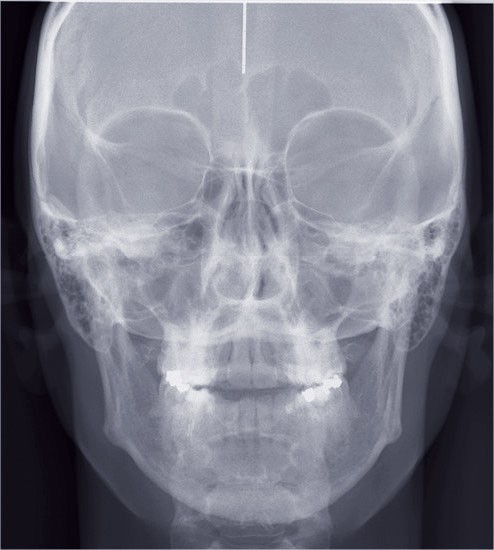

Les empreintes ont été réalisées en sillcone wash technique et adressées au laboratoire Insignia. Actuellement, nous réalisons ces empreintes à l’aide de la caméra intra-orale Lythos et la fiche patient est initialement créée sur la caméra. Le transfert des empreintes au laboratoire est immédiat et le risque d’erreurs considérablement réduit (fig. 4 à 6).